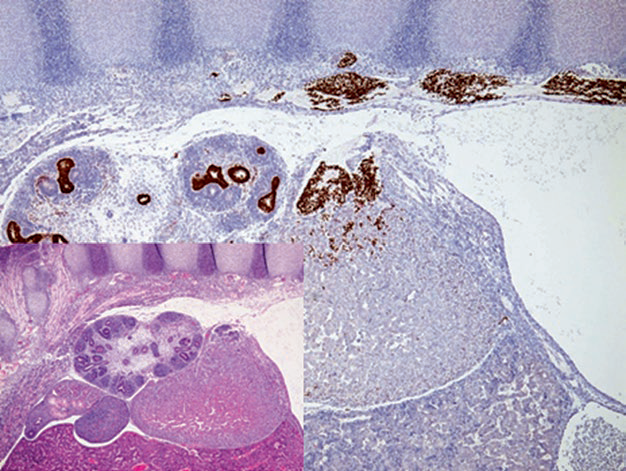

图4. 12周胚胎组织切片,免疫组化GATA-3标记椎旁神经嵴中的交感神经母细胞。这些细胞会迁徙入原始肾上腺的背内侧、形成肾上腺髓质;GATA-3还可标记肾脏集合系统中的尿路上皮。